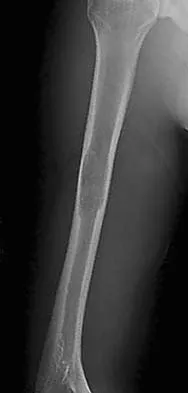

Figure 26a shows the radiograph of a 55-year-old woman who has pain in her right leg after falling. Laboratory studies reveal an elevated alkaline phosphatase level. A biopsy specimen from the proximal tibia is shown in Figure 26b. What is the most likely diagnosis?

Explanation

Paget's disease of bone is a metabolic disorder of bone remodeling. The normally coupled process of bone resorption and deposition is lost, resulting in excessive localized bone resorption and compensatory increased bone formation. Pagetic bone tends to be more brittle; therefore, it is susceptible to pathologic fractures and subsequent deformities. Lander PH, Hadjipavlou AG: A dynamic classification of Paget's disease. J Bone Joint Surg Br 1986;68:431-438.